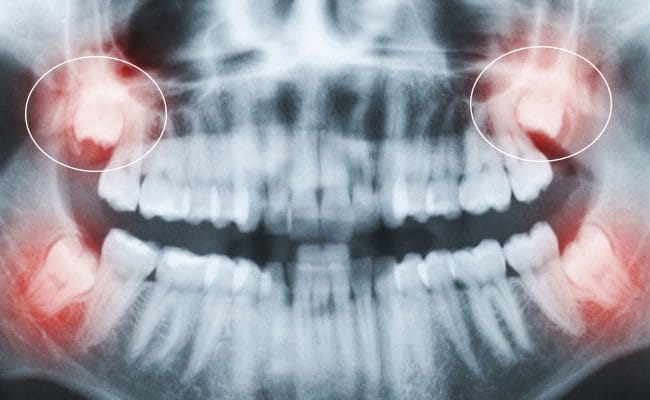

- Răng khôn mọc lệch, mọc ngầm: Cả 4 răng đều có dấu hiệu mọc lệch, đâm vào răng số 7, gây đau đớn, viêm nhiễm hoặc có nguy cơ làm hỏng các răng bên cạnh.

- Công nghệ hiện đại: Nha khoa được trang bị hệ thống máy móc tiên tiến như máy chụp phim CT Cone Beam 3D giúp xác định chính xác vị trí, hình dạng và hướng mọc của răng khôn, từ đó lên kế hoạch điều trị tối ưu. Đặc biệt, công nghệ nhổ răng khôn bằng máy Piezotome sử dụng sóng siêu âm giúp giảm thiểu tổn thương mô mềm, ít sưng đau và đẩy nhanh quá trình lành thương.